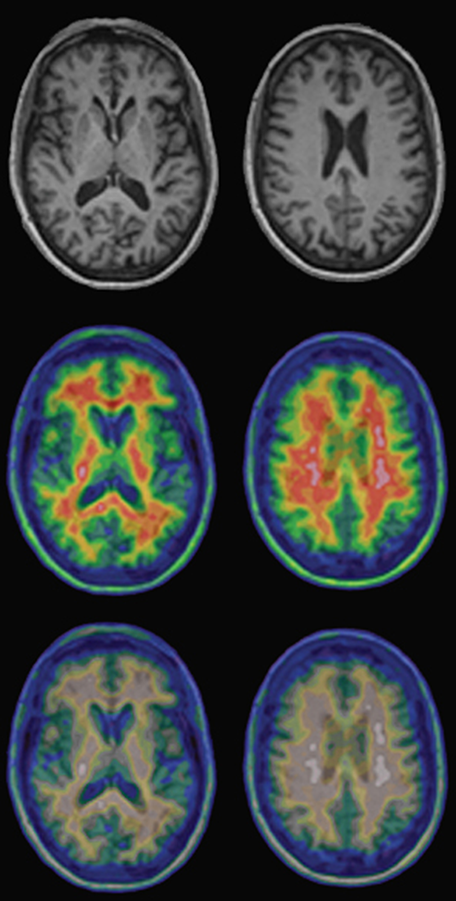

Figure 15-03:

Top: Regular T1-weighted gray-scale MR images of a healthy volunteer.

Center and bottom: PET-MRI fusion images of the same per­son. The upper row of the pseudo-color ima­­ges shows the normal images; the lower row shows the same ima­ges as seen by a person with red-green deficiency (deu­ter­ano­maly).